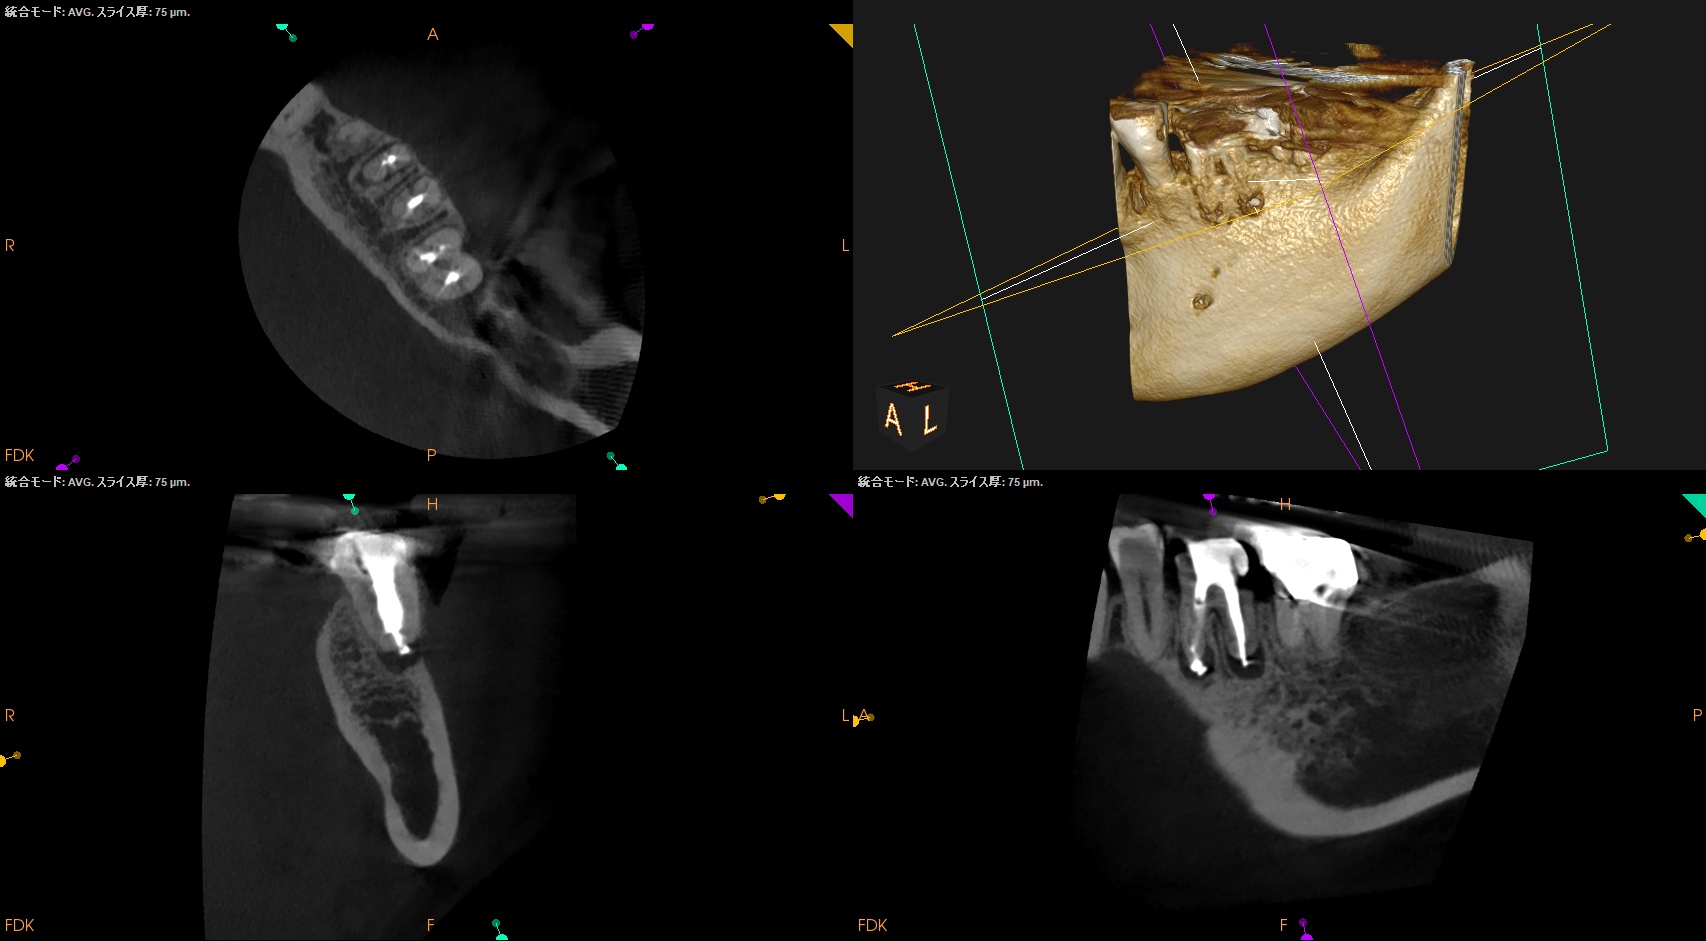

CBCT(2025.9.16)

MB

ML

D

MにもDにも病変がある。

B

頬側の骨がない。

これが圧痛に対する反応の原因だ。